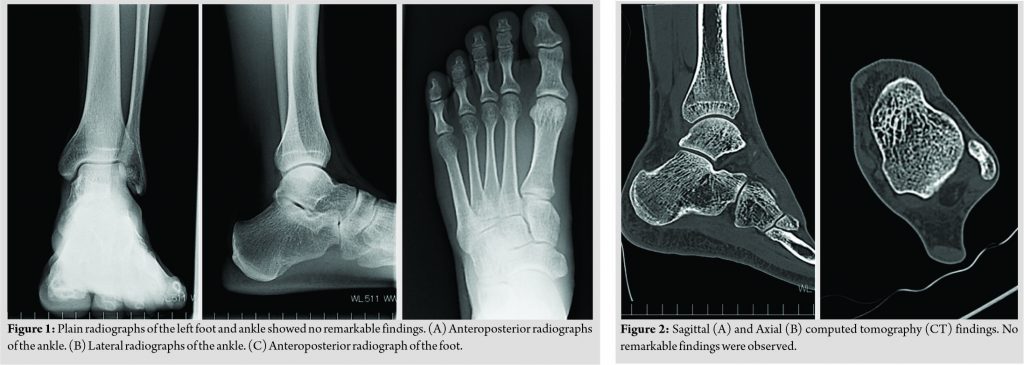

Physical examination revealed tenderness on the posteromedial side of his left ankle. His great toe was locked in the flex position when he actively flexed it. It could be corrected by passive dorsiflexion, associated with local pain, clicking, and popping sounds at the posterior ankle. Neurovascular examination and range of foot and ankle motion were normal. Neither radiographs nor computed tomography (CT) of his left foot and ankle revealed remarkable findings, such as osseous lesions, indicating the cause of his symptoms (Fig. 1a-c and 2a, b). Magnetic resonance imaging (MRI) indicated effusion in the tendon sheath of the FHL and the possibility of a partial tear of the FHL (Fig. 3a, b). Since the patient’s symptoms were not relieved with non-surgical treatments, including the injection of local anesthesia and physical therapies, he received surgery. We hypothesized that the scar tissue secondary to the partial tear of the FHL may have been irritated at the retrotalar pulley below the sustentaculum tali, where the FHL glides.